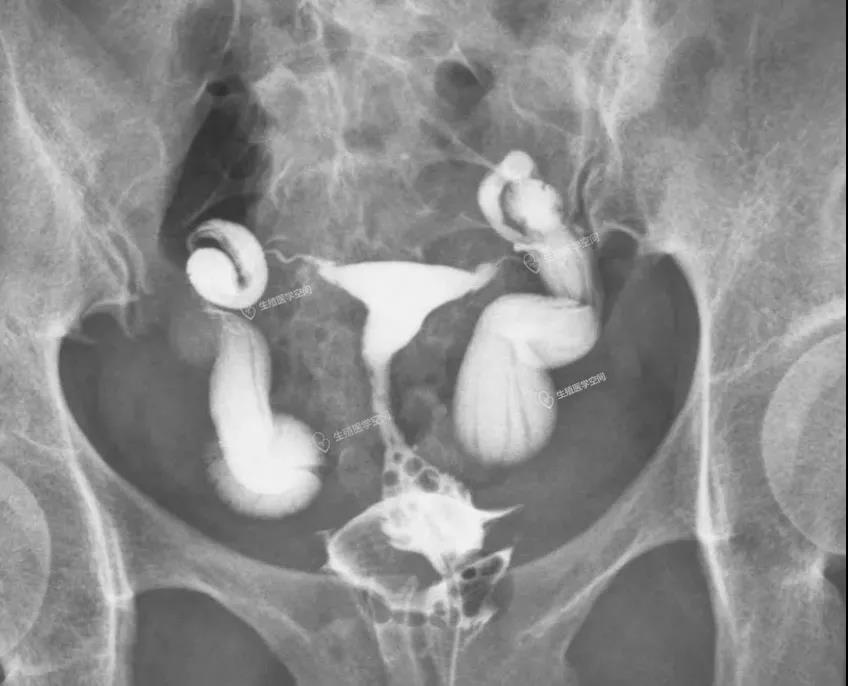

病例3 女 22岁 继发不孕,子宫输卵管造影发现双侧输卵管伞部阻塞。男方检查均正常。通过造影片初步评估输卵管粘膜功能好,于是做腹腔镜手术。术后第5个月怀孕,后来足月妊娠,自然分娩一健康婴儿。